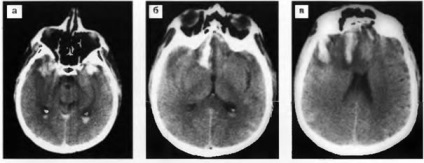

Ábra. 23. Diffusion axonok sérülés a corpus callosum. T2-súlyozott MRI: növekvő jel rész a corpus callosum görgő, szubdurális vérömleny a frontális.

Ábra. 24. Diffúziós axonális agysérülés. T2-súlyozott MRI (a, b) - részletekben enyhén csökkent perifocal jel hiperintenzív jel a jobb lábbal, és a bal agy fele görgő callosum, szubdurális vérömleny a jobb Front-temporális terület; a - MRT (sorozat szeletek) módban DBU: megnövekedett jelet részletekben alacsony jel punctata gócok az agyban lábak (d> s) és a görgő callosum.